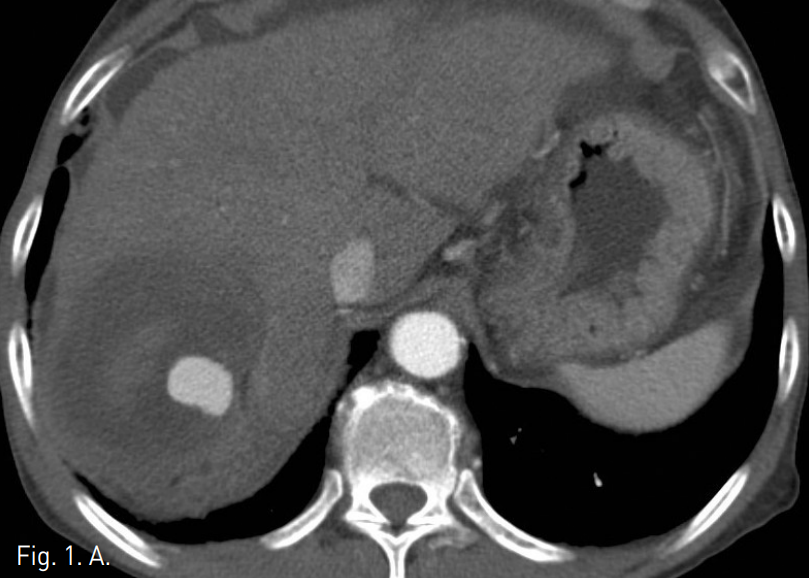

외래에서 시행한 복부 CT에서 간 우엽에 간동맥과 연결성을 보이는 2.5cm 크기의 가성 동맥류가 관찰되며 주위에 9cm 크기의 혈종이 있음. 간경변증을 보이고 있으나 간내에 간세포암종을 시사할만한 비정상적으로 조영증강되는 종괴의 소견은 관찰되지 않음(Fig. 1). 복부 MR에서 혈종의 뒤 안쪽으로 3.5cm 크기의 간세포암종으로 생각되는 병변이 관찰됨(Fig. 2).

Fig. 1

A, B. Axial (A) and coronal (B) CTimages of arterial phasereveal high density pseudoaneurysm and surrounded low density hematoma in the right lobe of the liver.

시술 2개월 후 시행한 조영증강 복부CT에서 우 간동맥에 의한 간내 가성동맥류는 보이지 않았고, 혈종은 약간 작아진 상태로 여전히 남아있었다(Fig. 4A). 간내종양은 lipiodol이 침착된 상태로 재발의 소견은 없었다(Fig. 4B).

Fig. 4

A, B. Two months after coil and chemoembolization, contrast-enhanced CT images show still remained hematoma and lipiodol Haden lesion without pseudoaneurysm.